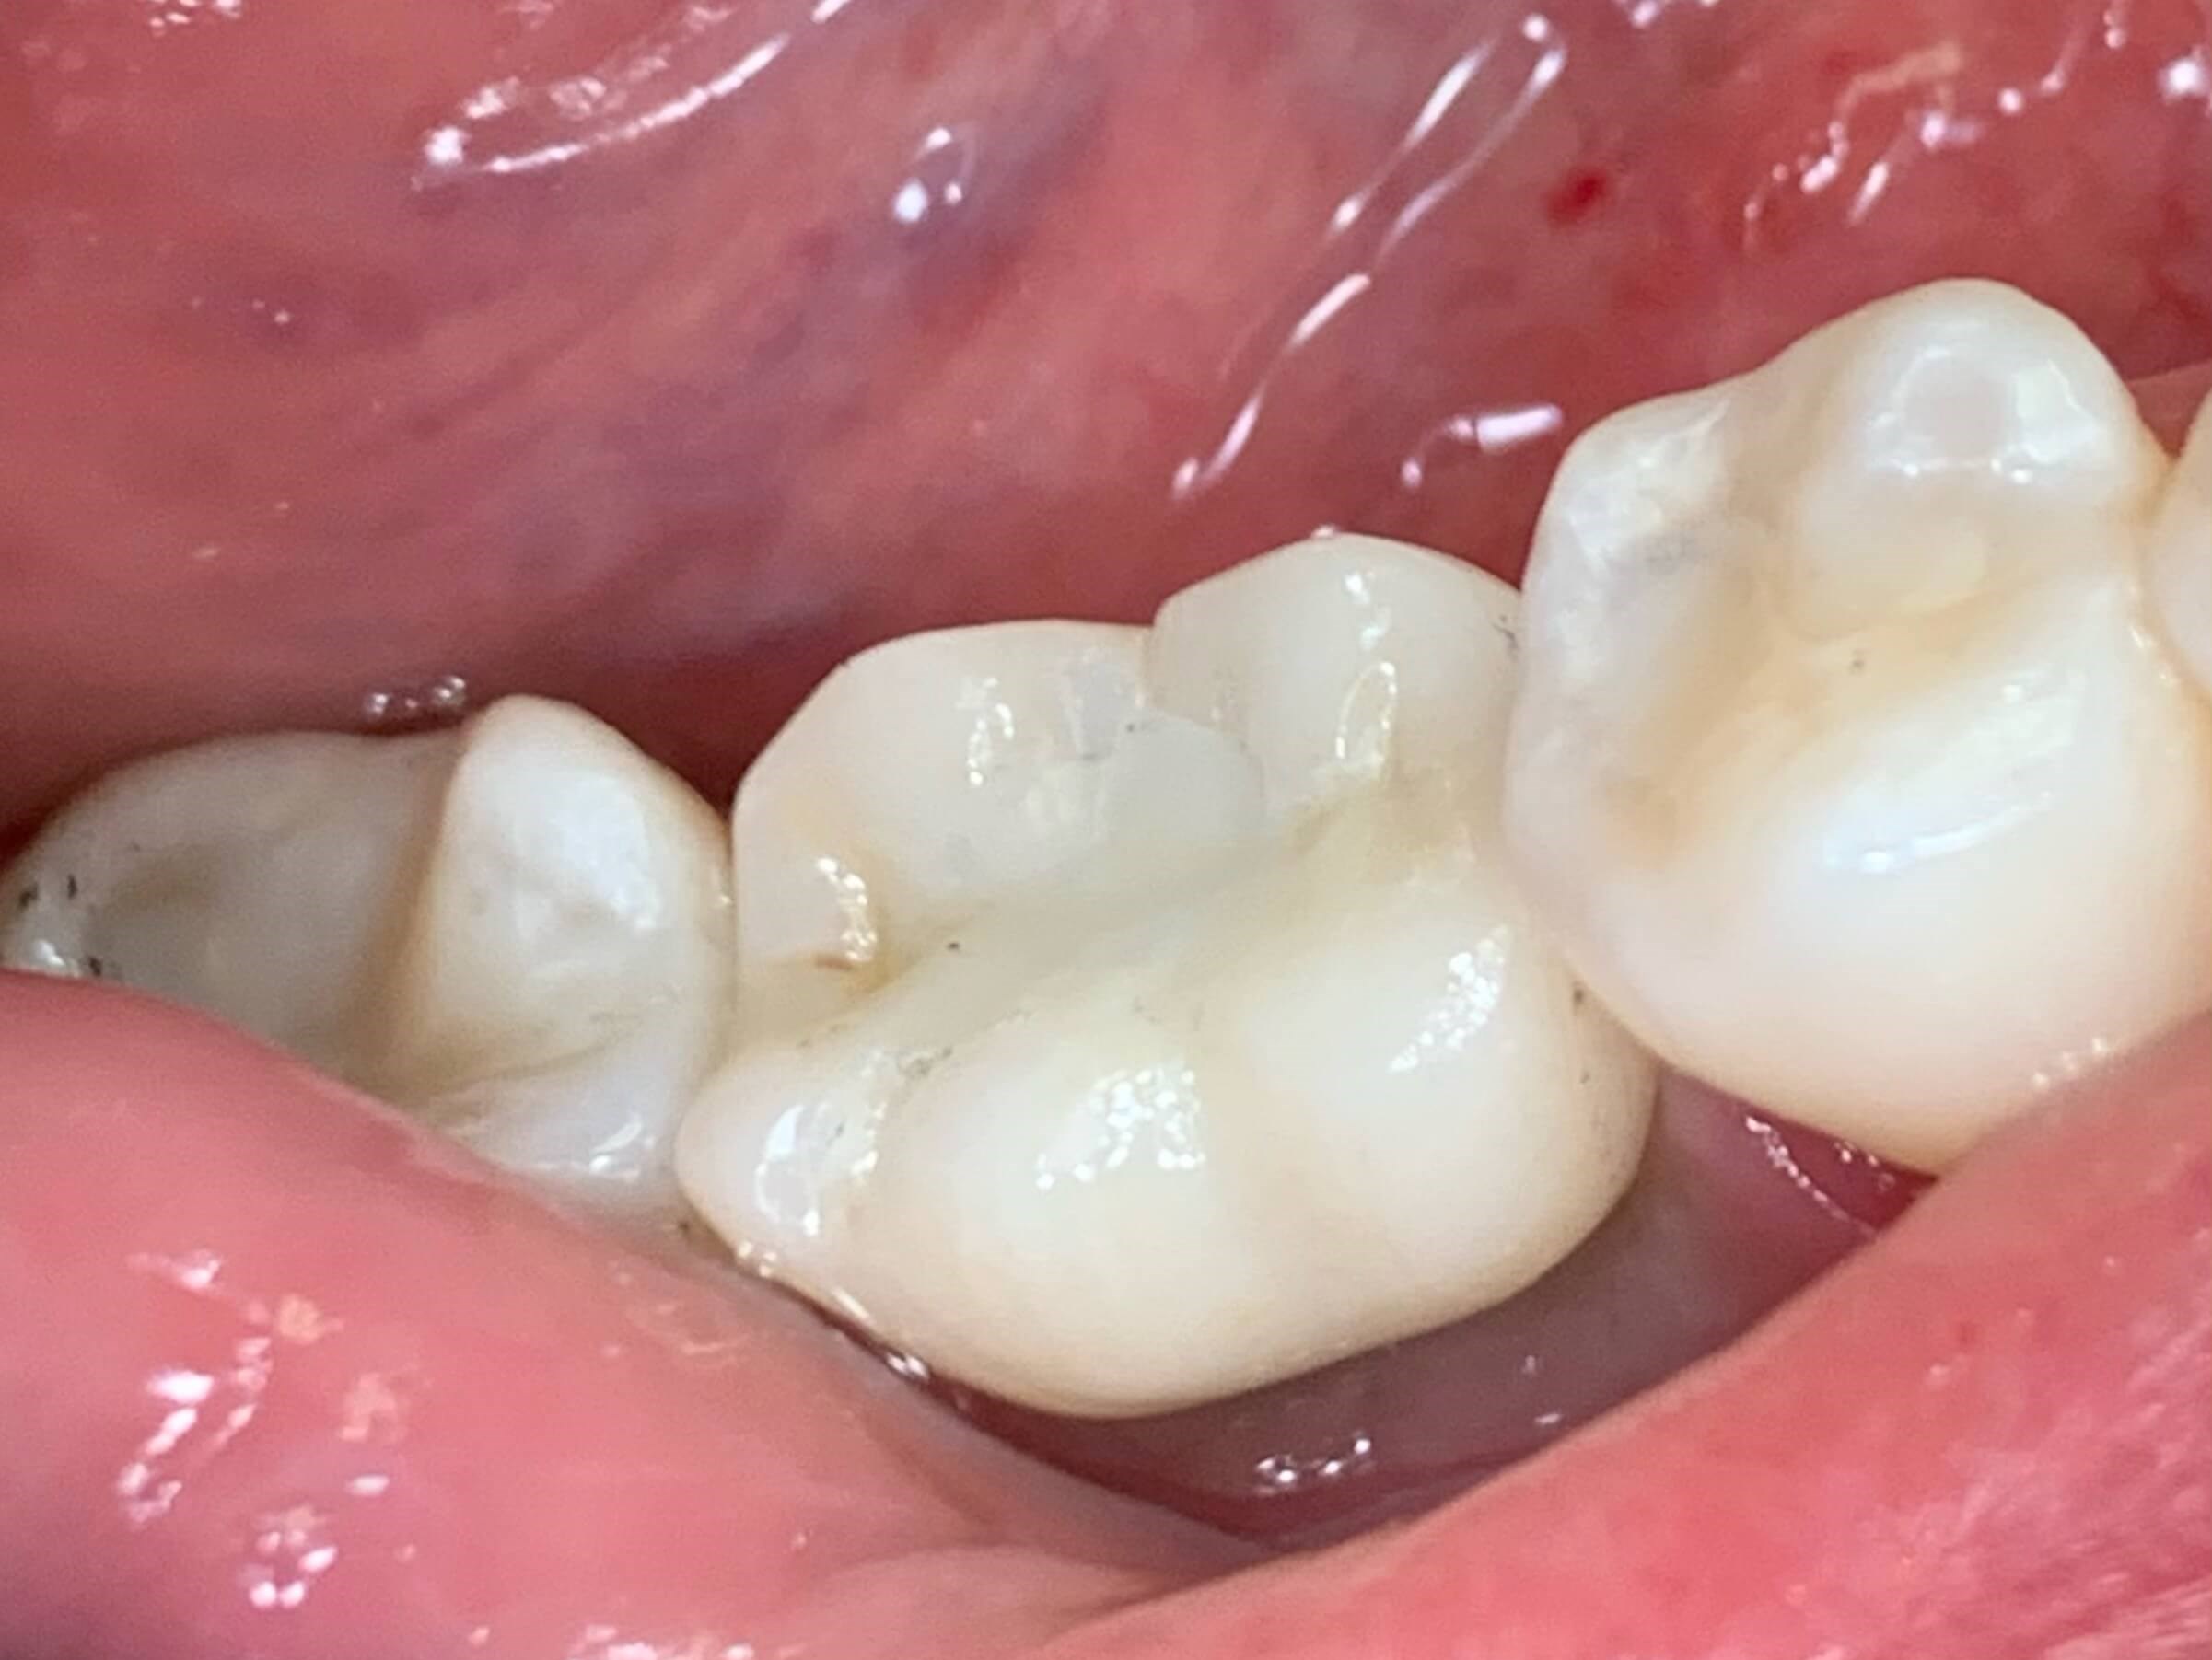

Custom Implant Crown

Procedure Details